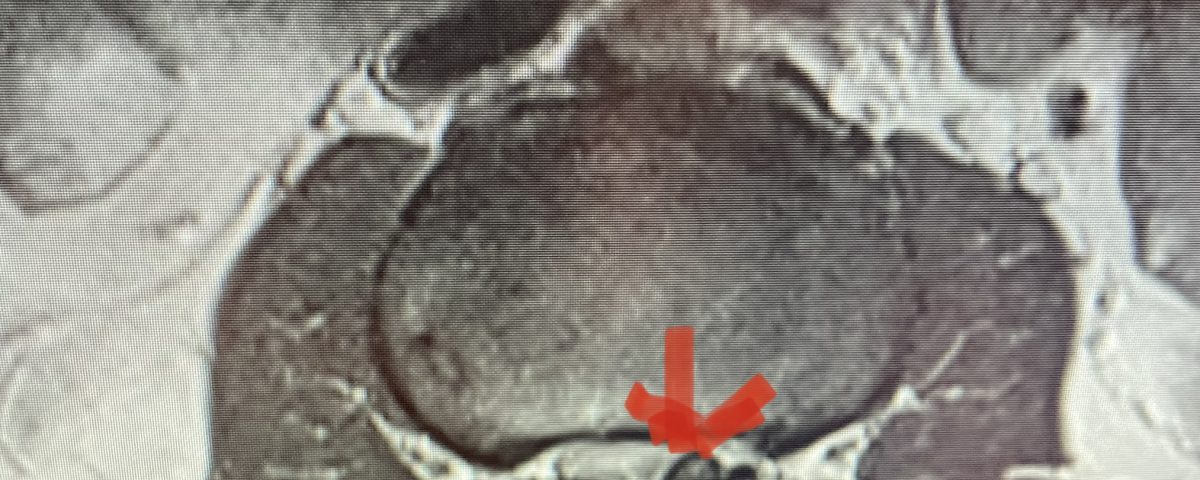

Figure 1: Axial lumbar spine images demonstrating the descent of the nerve root below the subarticular recess as it rounds the pedicle and enters the neural foramen. On the left shows the normal anatomy and on the right showing the descending nerve root being compressed in the lateral recess by a hypertrophied superior process with medial protrusion.

Figure 5: Axial T2-weighted MRI demonstrating severe bilateral lateral recess stenosis secondary to thickened ligamentum flavum. Notice the prominence of the left ligamentum in the subarticular recess.